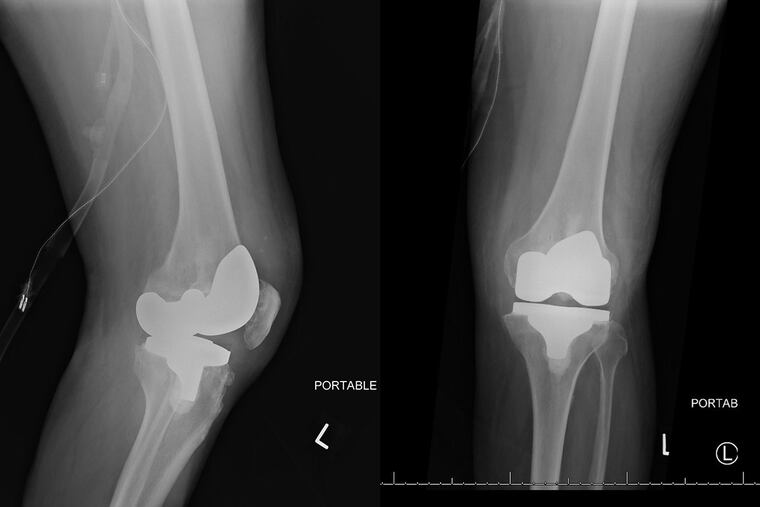

When he got to Jefferson Hospital, his left knee — which had the joint replacement — was warm and red, and it was painful for him to bend and straighten it. By now, our patient was so ill that he had to be transferred to the intensive-care unit. Radiographs showed severe soft tissue swelling, though the implant was where it should be, and there was no evidence of it loosening.